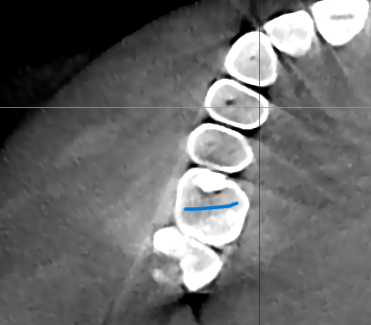

На 6 жевательном зубе справа на верхней челюсти в 2020 году поставлена пломба. Фото прилагаю. На КТ от 2024 года я сам нашел полость под пломбой, это вторичный кариес? Врач который смотрел КТ об этом не упоминал. Еще вопрос зуб же не депульпированный?

Все эти годы зуб не беспокоил. КТ скрины прилагаю.

Ответ №1 - да!

Ответ №2 - да!